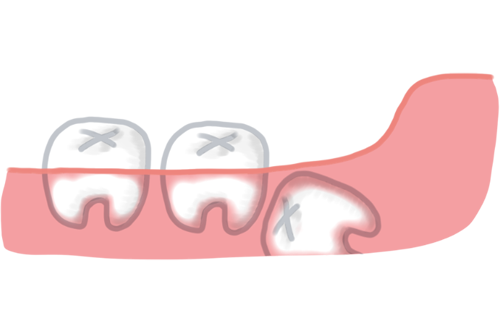

親知らずが部分的にしか歯茎から出ていない状態では、歯の頭部分が歯茎に覆われた状態(歯冠周囲の炎症)が繰り返されることがあります。これを「智歯周囲炎(ちししゅういえん)」といいます。

智歯周囲炎が起きると、次のような症状があらわれます。

炎症が強い時期には抜歯が行えないため、まず抗菌薬などで炎症を落ち着かせてから抜歯を検討することが一般的です。繰り返す智歯周囲炎は抜歯の適応となる場合が多く、症状が出たら早めに歯科を受診することが大切です。

奥歯の歯茎が腫れているイメージ